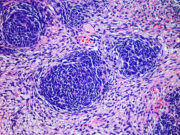

neue Forschungsergebnisse zeigen, wie Nierenkrebs bei Kindern entsteht, die eine Veranlagung für den Wilms-Tumor haben. Dazu haben die Autoren einer aktuellen Studie mehrere hundert Gewebeproben dieser Tumorart genetisch kartiert, darunter auch von Kindern mit einer genetischen Veranlagung, von denen einige frühe Symptome aufwiesen. Es zeigte sich, dass verschiedene Arten genetischer Prädispositionen und teils komplexe strukturelle Veränderungen von Chromosomen die Tumorbildung verursachen können. Co-Erstautorin Dr. Taryn Treger kommentiert: „Unsere Forschung zeigt, dass sich Krebserkrankungen auf unterschiedliche Weise entwickeln, je nachdem, welche genetische Veränderung ihnen zugrunde liegt.“

Genetische Veranlagung für die Entwicklung von Nierentumoren bei Kindern entschlüsselt

Neue Forschungsergebnisse zeigen, wie Krebs bei Kindern entsteht, die eine Veranlagung für den Wilms-Tumor haben. Dies könnte dazu beitragen, die Entwicklung von Tumoren vorherzusehen, bevor sie sich vollständig ausbilden, oder neue, zielgerichtete Therapien zu entwickeln.